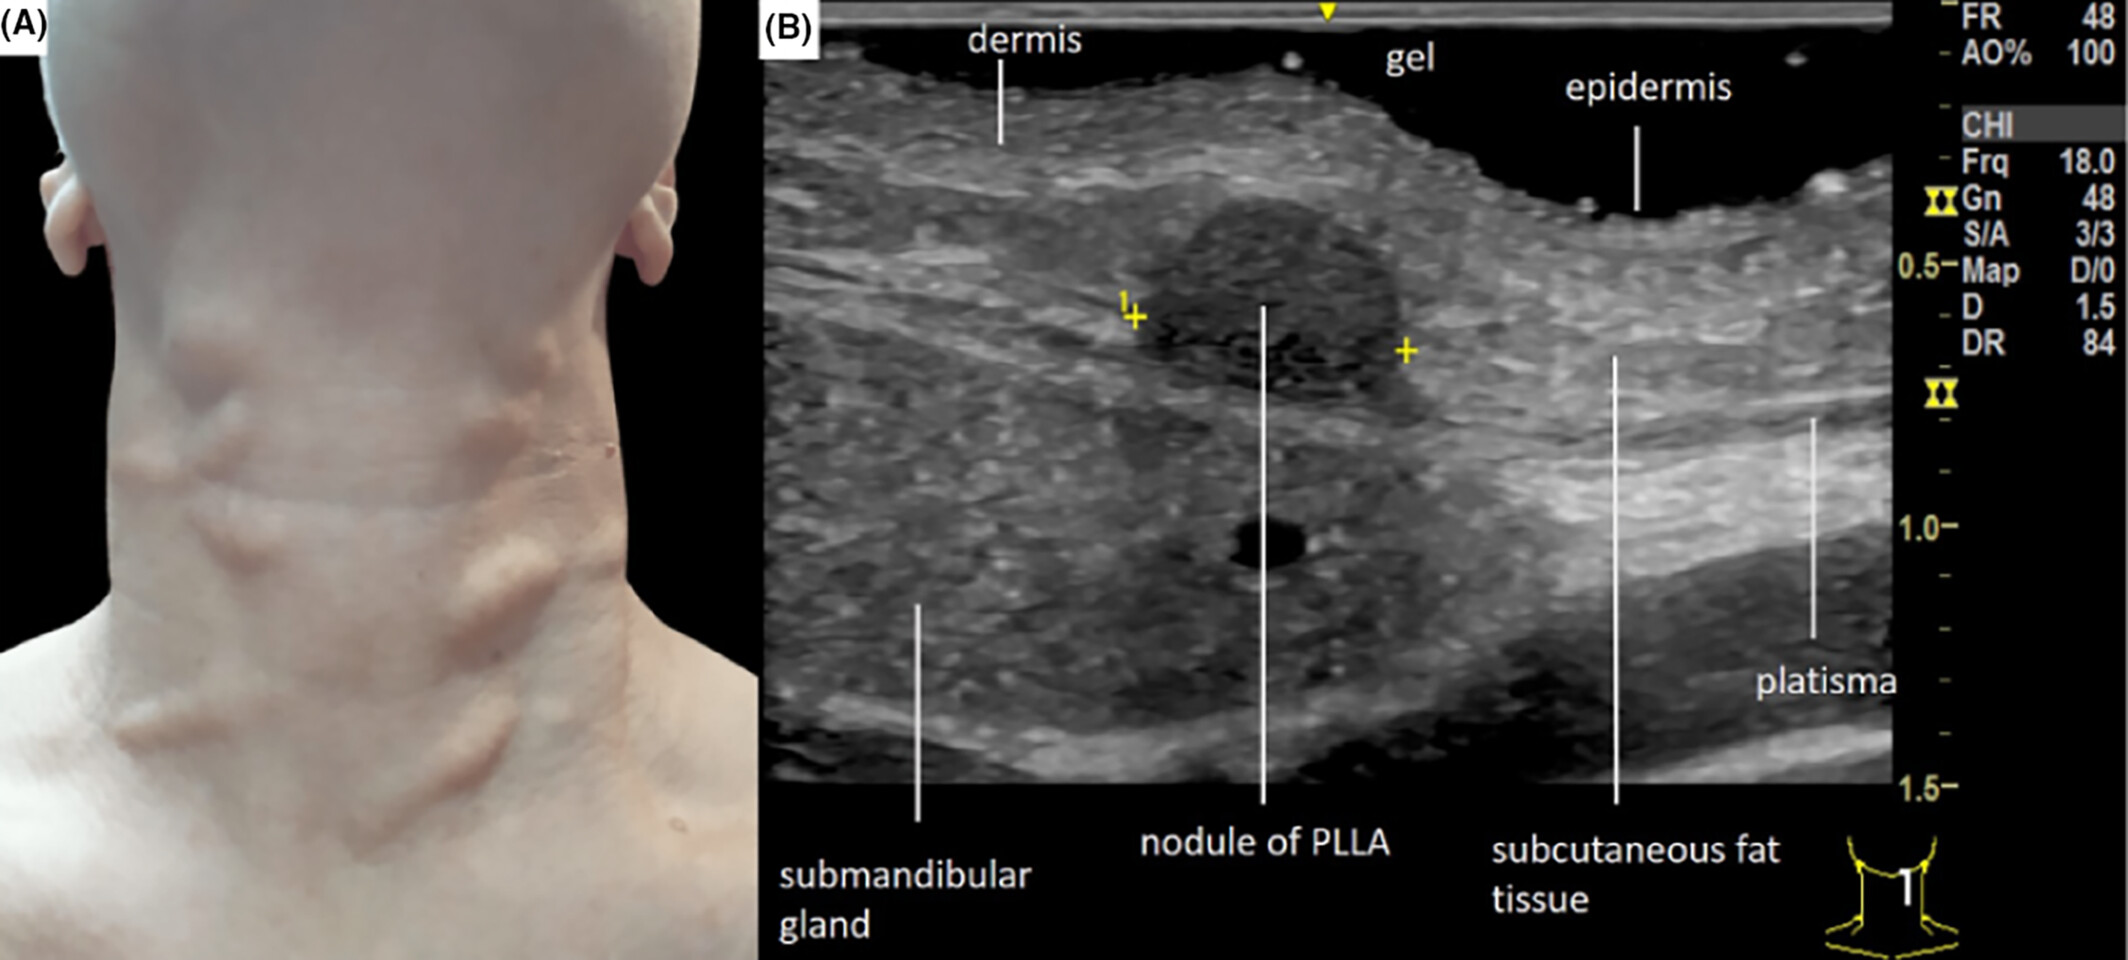

– Nodules may form months or even years post-injection.

– Can be firm, palpable, and sometimes painful or visible.

– Management often requires intralesional steroids or surgical excision.

– A 2019 study in *Dermatologic Surgery* reported late-onset nodules in up to 7% of patients treated with PLLA.